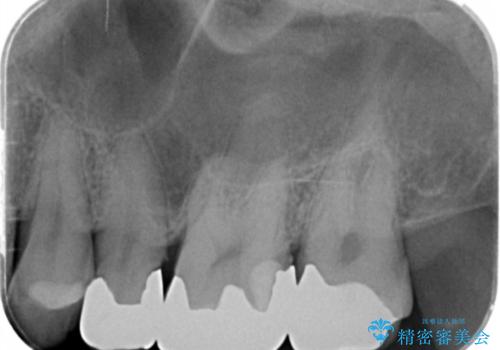

銀歯を丁寧に除去すると、銀歯の下で虫歯の再発やセメントの劣化が確認されたので、拡大鏡・マイクロスコープを用いて虫歯のみを丁寧に取り除いたのち、精密なセラミッククラウンの製作を進めます。

拡大鏡・マイクロスコープを用いて虫歯を丁寧に除去することで、健全な歯質や神経を守ることにつながります。